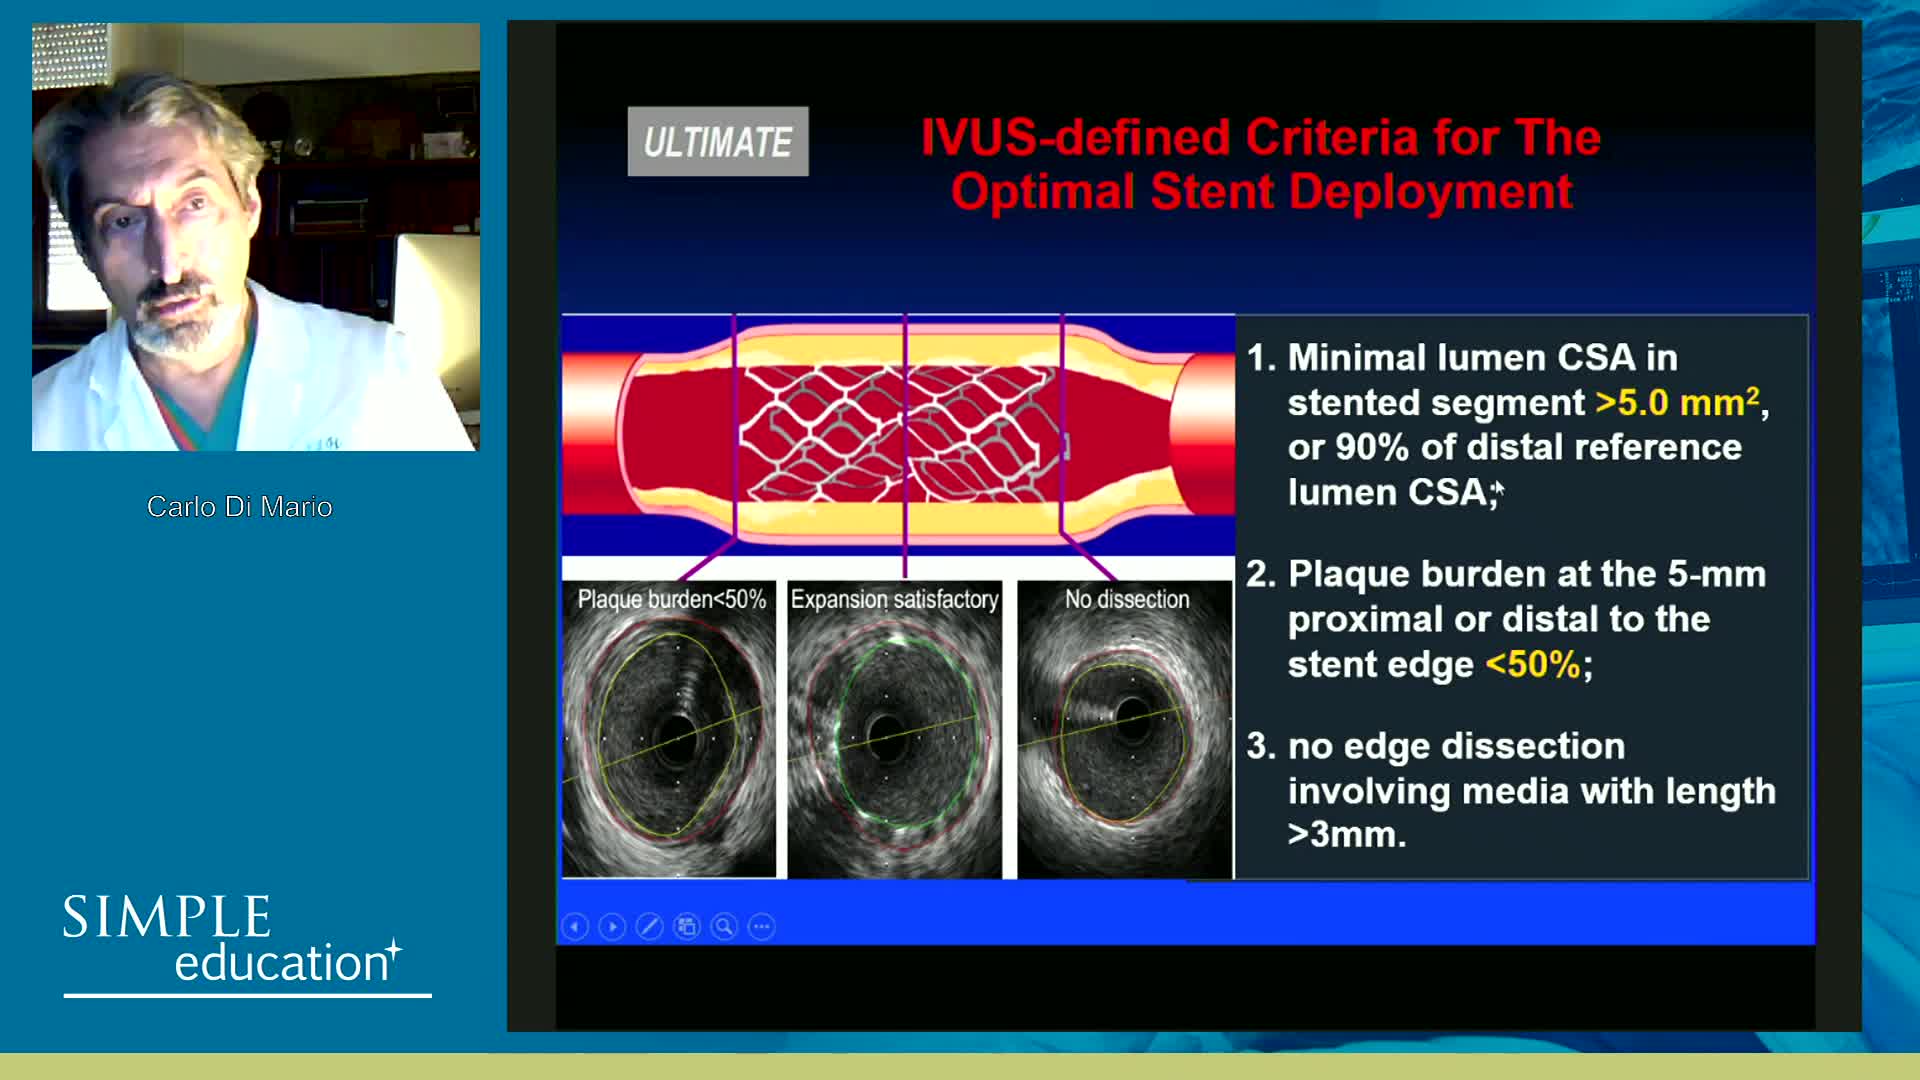

How to perform good co-registration measurements using iFR and IVUS - Prof Carlo Di Mario